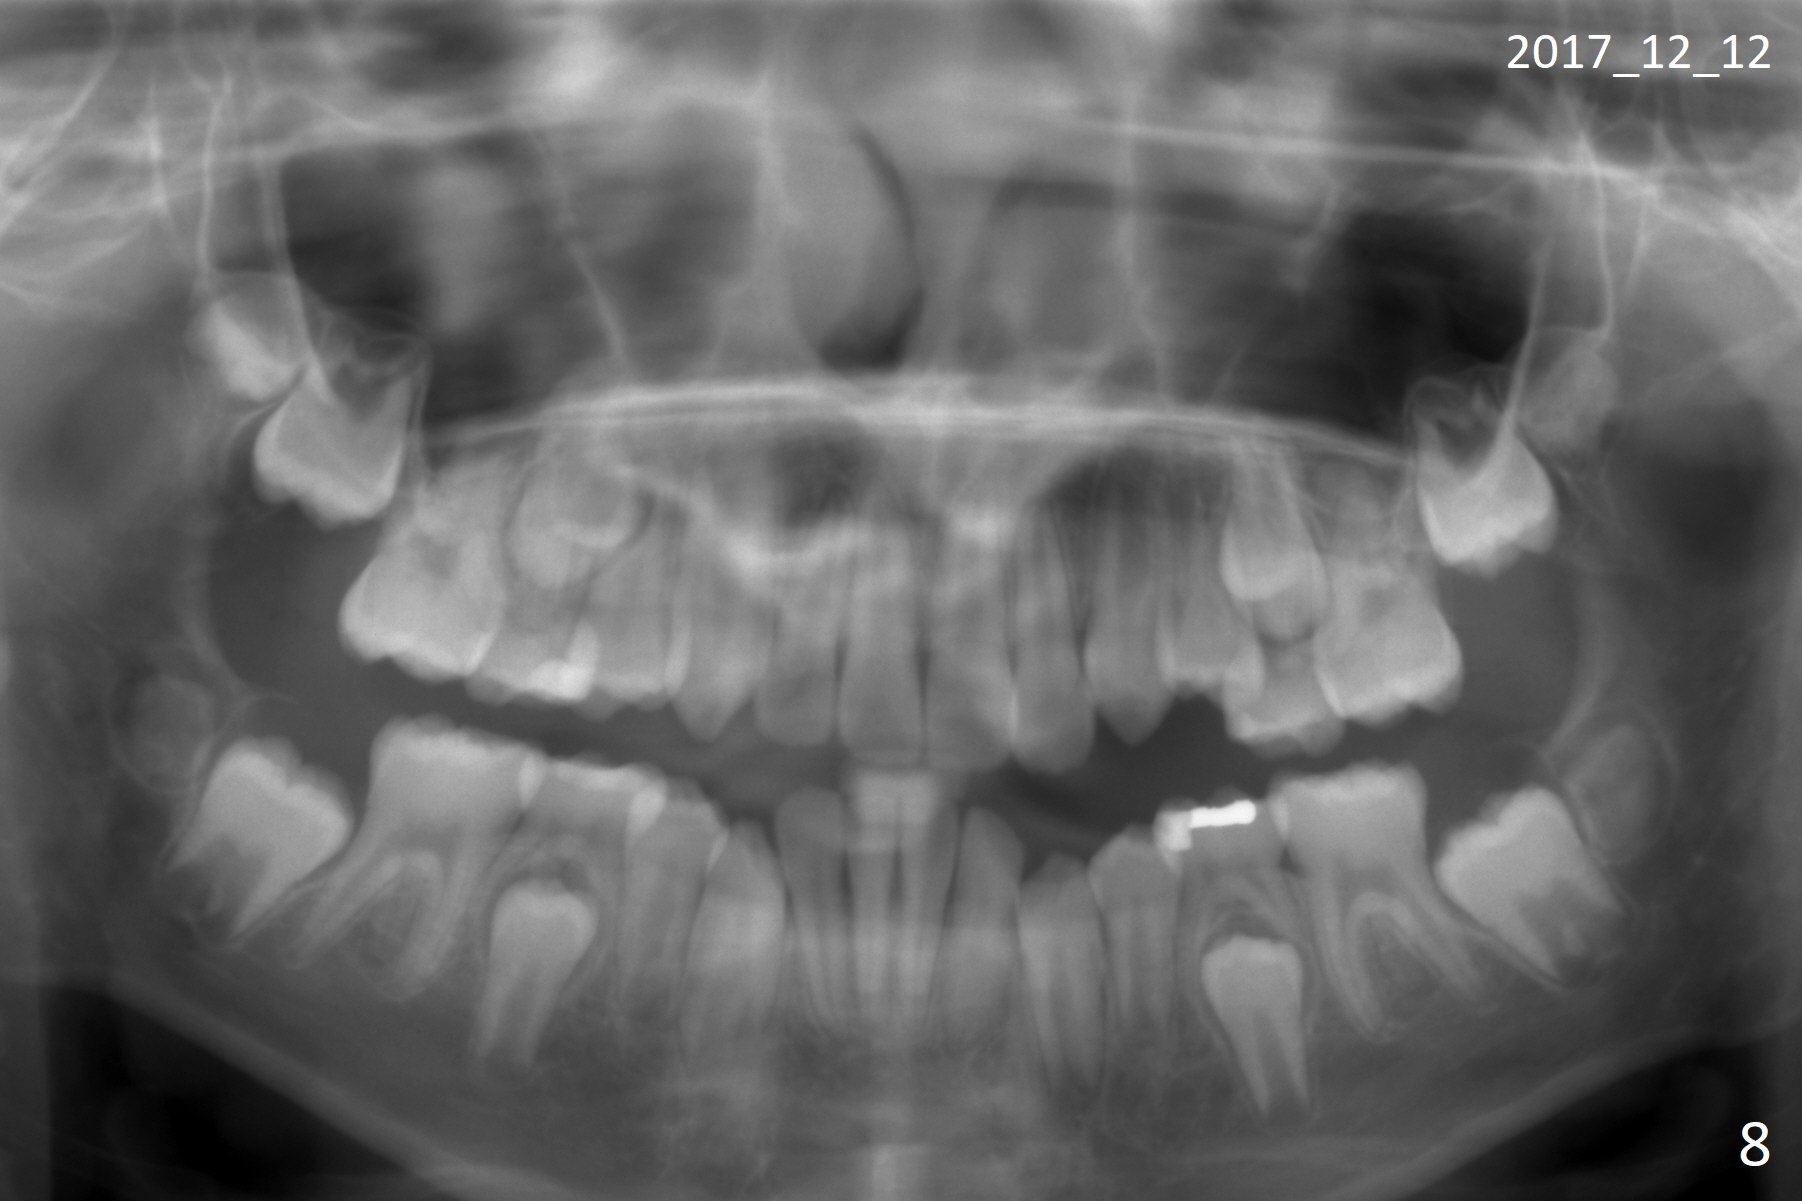

Shallow Overbite

A 12-year-old man has mild lip protrusion (Fig.1,6,7). Orthodontics will be conducted without extraction. Unlike his elder brother, the overbite is shallow. With anterior bracket differential (4-4-5 mm) and mild bimaxillary protrusion, open bite will be created? Or 4-4-4.5mm scheme should be adopted to avoid open bite?